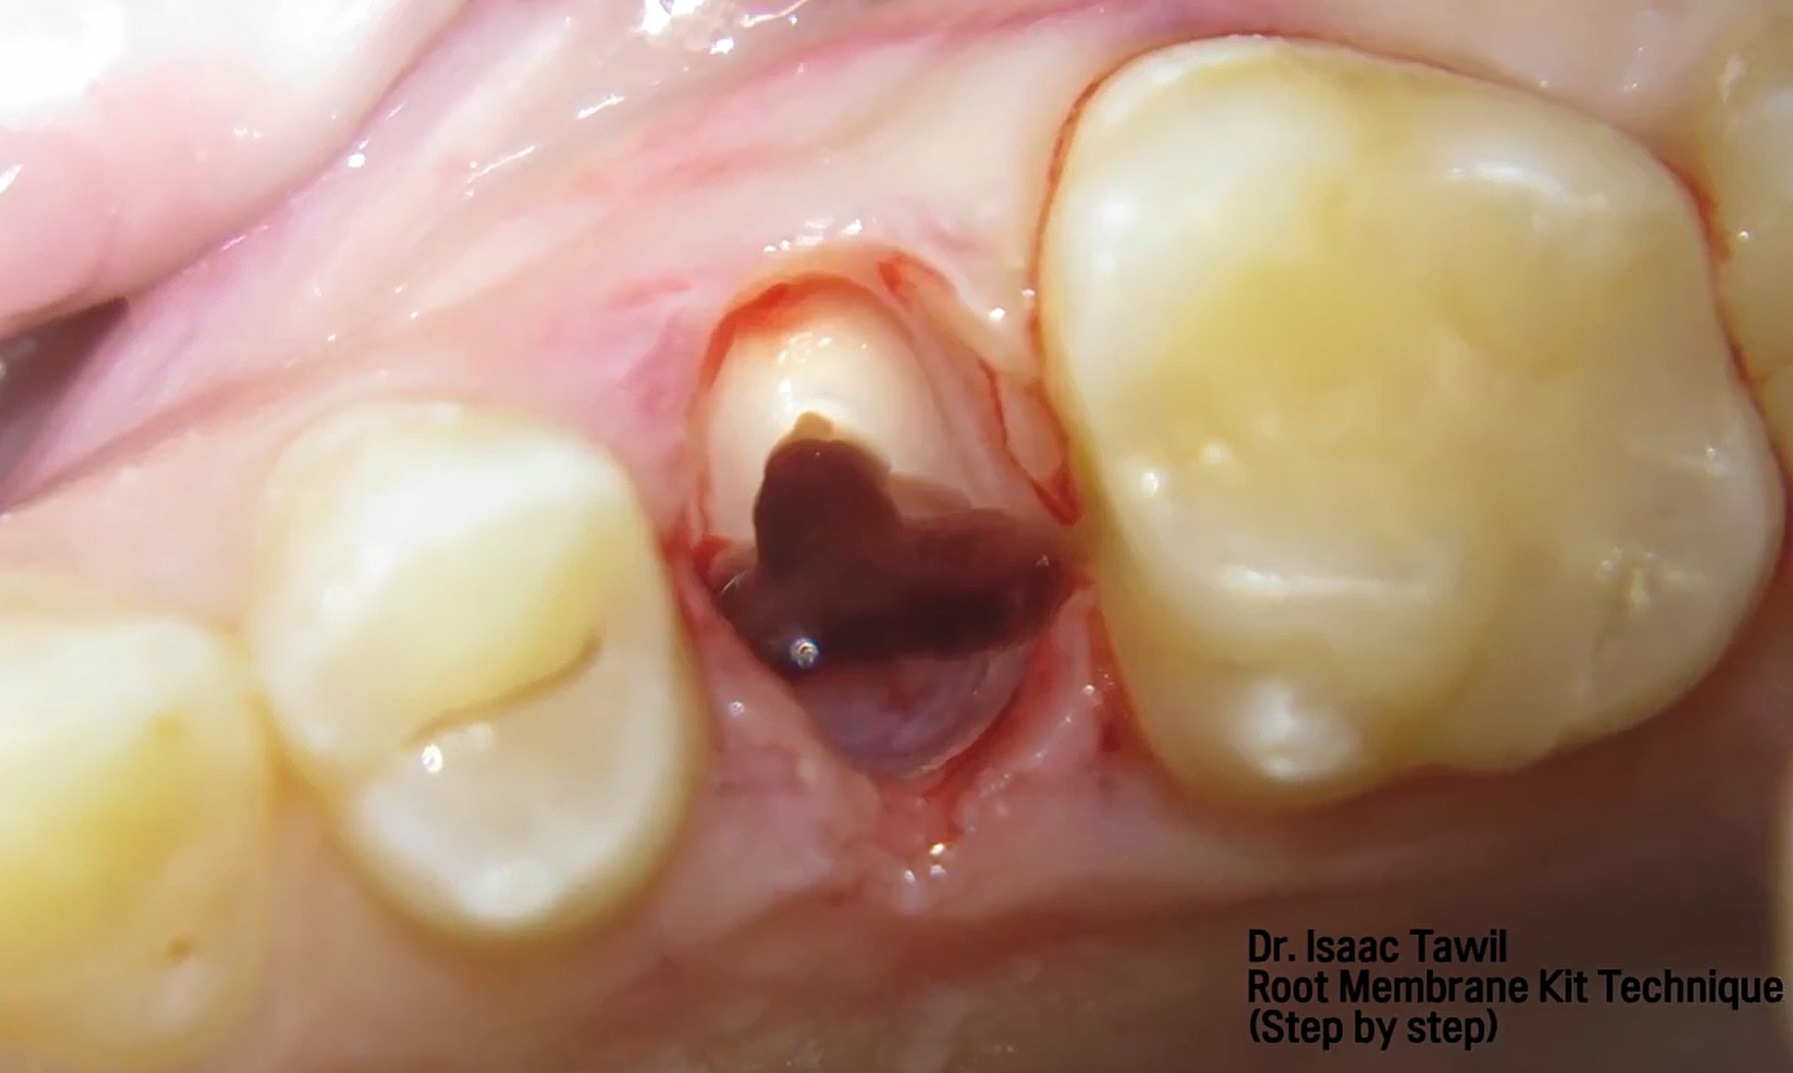

#11,#12,#23,#24 Root Membrane Technique with Digital R2GATE Surgery

#11,#12,#23,#24,Aesthetic zone,AnyRidge,Customized Abutment,Digital Guided Surgery,Guided surgery,Initial stability,Maxillary Anterior,Maxillary Posterior,MEGA ISQ,MiNi,PMMA crown,R2GATE,R2GATE Surgical Kit(AnyRidge),Root Membrane,Root Membrane Kit,video